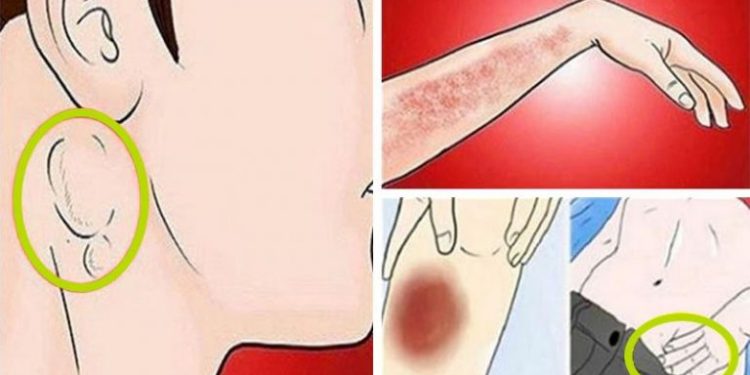

Njihuni me shenjat që tregojnë se kanceri po “rritet” shumë në trupin tuaj

Njihuni me shenjat që tregojnë se kanceri po “rritet” shumë në trupin tuaj

Mjekët parashikojnë që mijëra vdekje mund të shmangen çdo vit nëse kanceri diagnostikohet herët. Në…